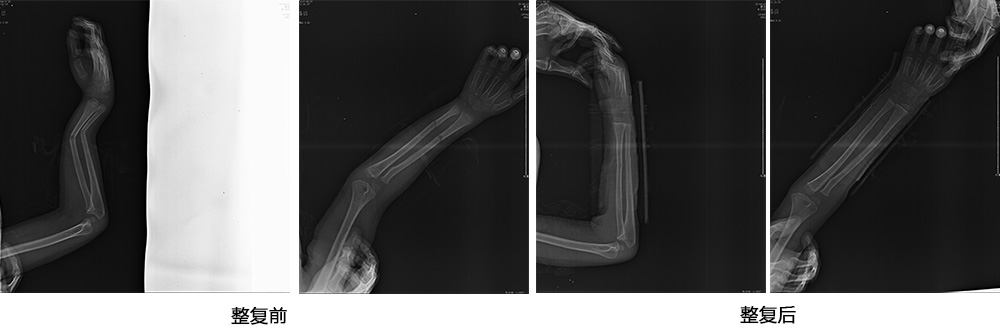

傳統(tǒng)手法整復(fù)病例影像

CR94676